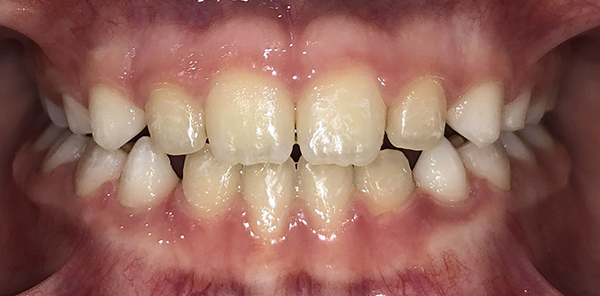

Actual Patient: Alexander

Alexander Before 4 Alexander After 4

Severe “Underbite”, Narrow Jaws, Adult Teeth Not Growing In

Alexander Before 1 Alexander After 1

Front View

Top View

Right & Left Sides